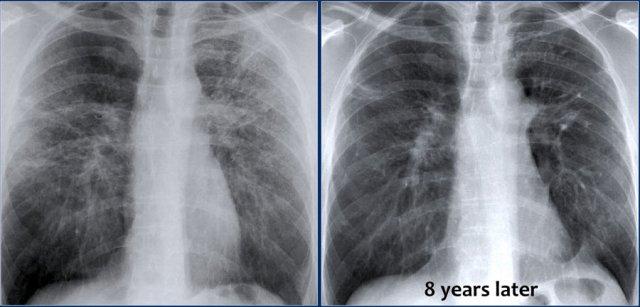

Bệnh nhân này nhập viện lần đầu với phim X quang ngực bên trái.

Hãy quan sát kỹ các hình ảnh trước.

Các dấu hiệu bao gồm:

- Các đám mờ bờ không rõ lan tỏa, có thể là các vùng đông đặc nhỏ.

- Hang ở thùy trên phổi phải.

Có thể nhận định đây là tái hoạt của lao tiềm ẩn.

Cấy đờm dương tính với vi khuẩn lao.

Phim X quang ngực chụp vài năm sau (bên phải) cho thấy:

- Xẹp thùy trên phổi phải

- Lệch khí quản

- Xơ hóa và tạo hang ở phần còn lại của thùy trên

- Xơ hóa tối thiểu và tạo hang ở thùy trên phổi trái.

Điều này được đánh giá rõ hơn trên CT.